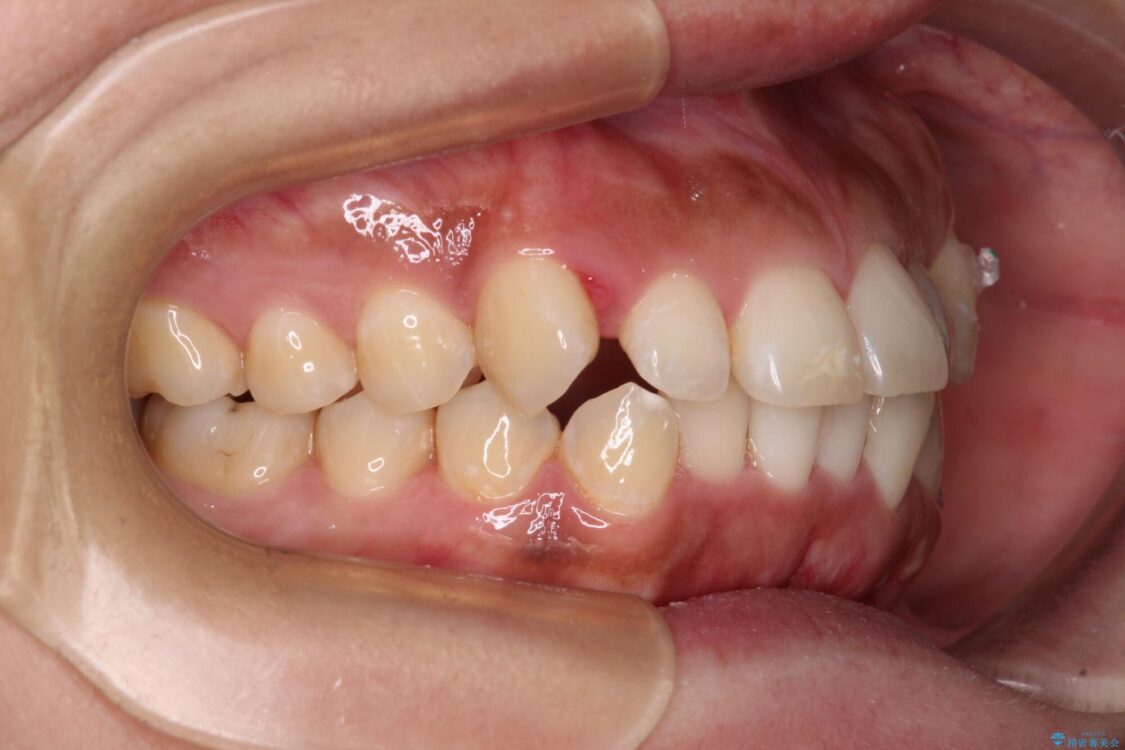

治療後

• 【モニター】カリエール・ディスタライザーを併用した八重歯のインビザライン矯正 治療後画像

カリエールディスタライザーを併用したことで、すっきりとした口元になり、上下の正中を合わせることができました。